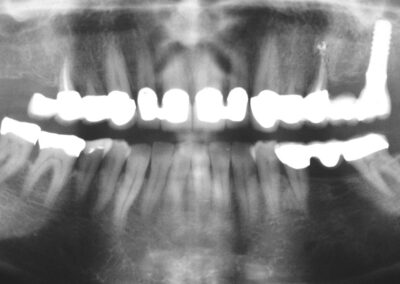

Präprothetisches Ausgangs-OPT im Juni 1991 (Klick!)

Die relativ junge Patientin stellte sich damals mit einem Abszess in regio 17/18 vor. Der gesamte Oberkiefer sah damals schon nicht gut aus. Typischer Röntgen-Befund einer starken Bruxerin (Ein-Blick-Diagnose) mit passender psychosozialer Anamnese. Heute würden wir so einen Fall sicher ganz anders angehen (sofortige Ex der beiden OK-Achter, sofortige EKR der beiden OK-Brücken mit WF nach sorgfältiger Desinfektion von 17, 15 25 und 27), sofortige Neuversorgung mit jeweiliger Verblockung inklusive der Vierer, wenn nicht sogar der Dreier, usw.) und hätten so den 17 und 27 sicher langfristig erhalten und die Erzeugung von Freiendsituationen mit an Sicherheit grenzender Wahrscheinlichkeit genau so langfristig vermeiden können. Aber damals waren wir noch so herrlich jung und unerfahren, und es handelte sich darüber hinaus ja auch um eine Bekannte……. Deshalb haben wir damls aus heutiger Sicht leider nur die rechte Seite neu versorgt, auf der die Beschwerden aufgetreten waren.

Immerhin hatten wir schon begriffen, welche fatalen Folgen „schlechte Gewohnheiten“ in einem menschlichen Gebiss haben können, hatten bereits gelernt, ihre in einem solchen Fall aus unserer heutigen Sicht offensichtlichen Zeichen richtig zu deuten, hatten bereits Erfahrung mit den Segnungen der Timbuktu-Methode (schauen Sie einmal, wie sich die Situation am 15 über die Jahre gehalten, bzw. sogar trotz des Freiendbrückengliedes verbessert hat) und – das war wohl das Wichtigste- hatten der Patientin plausibel machen können, wie essentiell das konsequente Tragen einer Aufbissschiene ist, wenn man unter dieser Grunderkrankung leidet, nichtsdestotrotz aber seine Zähne erhalten möchte.